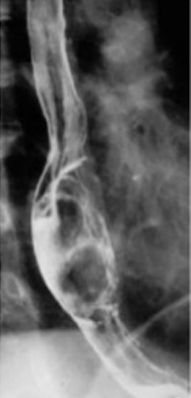

Image TOGD en double de contrast : Tumeur

intramurale bord lisse reduisent l /2 lumiere

de oesophage |

Leiomyome 1/3 inferieure de oesophge

: L lumiere de oesophge est redusent par une

refoulement reguliere de l muqueuse |